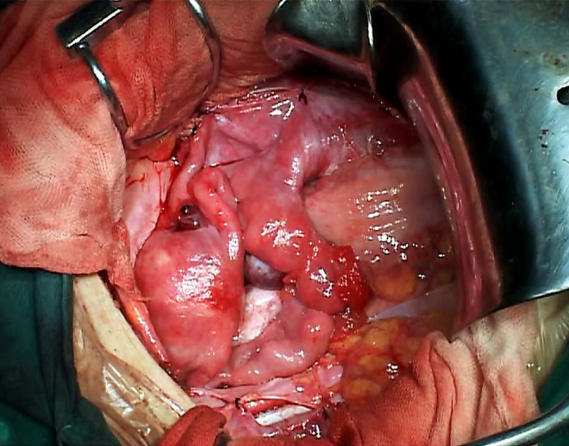

Ⅲ型即广泛子宫切除术标本 盆腔淋巴结切除术标本